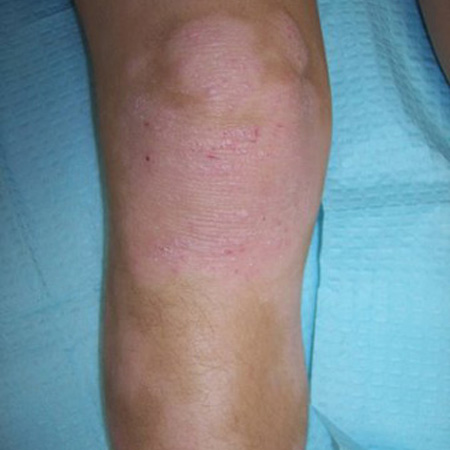

Children typically have involvement of flexures, particularly the wrists, ankles, and antecubital and popliteal fossae.[10][22]

In addition to the areas affected by acute disease, chronic eczema often affects the neck, upper back, and arms, as well as the hands and feet.[1][7][64][Figure caption and citation for the preceding image starts]: Lichenification of the popliteal fossa in a child with eczemaFrom the personal collection of A. Hebert, MD; used with permission [Citation ends].

lichenification

Thick, lichenified skin is evidence of chronic dermatitis.[49][Figure caption and citation for the preceding image starts]: Lichenification of the popliteal fossa in a child with eczemaFrom the personal collection of A. Hebert, MD; used with permission [Citation ends].